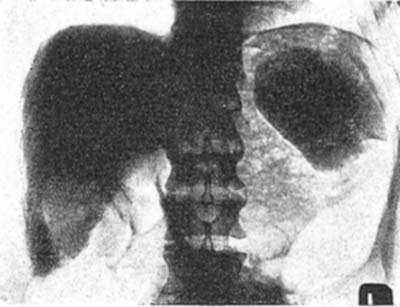

図2. トロトラスト静注による肝脾造影(hepatolienography).トロトラストが肝,脾に沈着し,高濃度に認められる.[2]

トロトラストは,ヨードにくらべて造影能がきわめて良好で,ヨードで問題となる静脈内投与における熱感,刺激性がほとんど無いため急速に普及した*.トロトラストの大きな特徴は,血管内投与するとから細網内皮系に取り込まれて肝,脾,リンパ節,骨髄に沈着し,そのままほとんど排出されないことで,生物学的半減期は約400年と推定される.このため,静注24時間以後に腹部X線写真を撮影すると肝,脾が高濃度に描出され,これは 肝脾造影法(hepatolienography)と呼ばれた[2](図2).この他,脳血管造影にも広く使われた[3](図3).投与量は,例えば肝脾造影の場合,25mLを隔日3回[→関連文献],脳血管撮影では1回8~10mLであった[3].